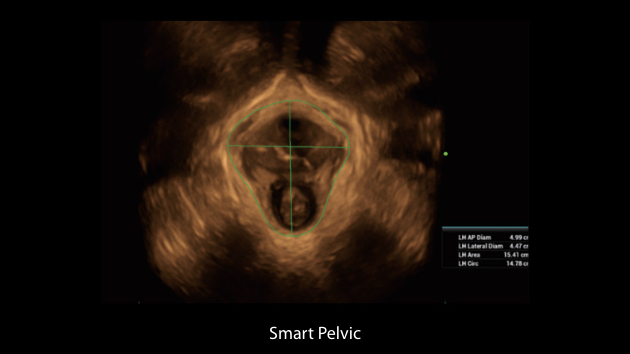

El sistema Nuewa I9, dise?ado exclusivamente para la atenciĂłn mĂ©dica neonatal y de mujeres, brinda una experiencia innovadora integral. Estas innovaciones se desarrollan sobre la base de un conocimiento profundo de situaciones clĂnicas complejas para proporcionar respuestas precisas y oportunas, una gran eficiencia y una experiencia de usuario extraordinaria.

La plataforma ZST+?es una innovaciĂłn extraordinaria que representa toda una evoluciĂłn en el ĂĄmbito de la ecografĂa. Transforma las mĂ©tricas ecogrĂĄficas de la formaciĂłn de haces convencional al procesamiento basado en datos de canal. Supera la limitaciĂłn tradicional de tener que equilibrar entre resoluciĂłn espacial, resoluciĂłn temporal y uniformidad del tejido, con lo que ofrece una calidad de imagen excepcional para soluciones de producciĂłn de imĂĄgenes infinitas con mejoras continuas.